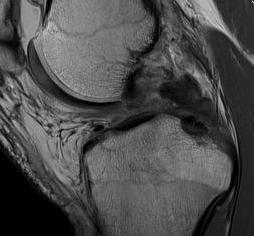

Posterior subluxation of tibia

Grade 3 PCL disruption - posterior tibia subluxed behind posterior aspect femoral condyles

MRI

PCL tibial avulsion

PCL femoral avulsion